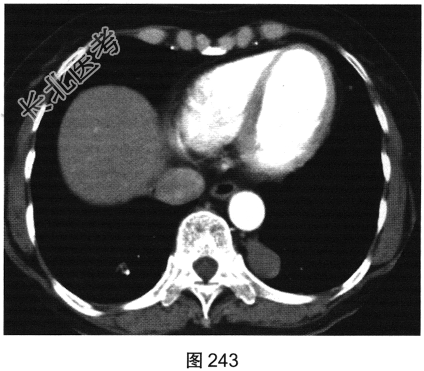

- 多项选择题3.[提示]患者增强CT如图243、图244所示。下述哪些征象的描述是正确的( )

A、可出现气液平面

B、增强扫描无明显强化

C、囊性病变也可表现为平扫高密度

D、MRI对本例病变的鉴别诊断没有帮助

E、如病灶内可见支气管穿行进入,则可定位在肺内

F、神经源性肿瘤常可见椎间孔扩大